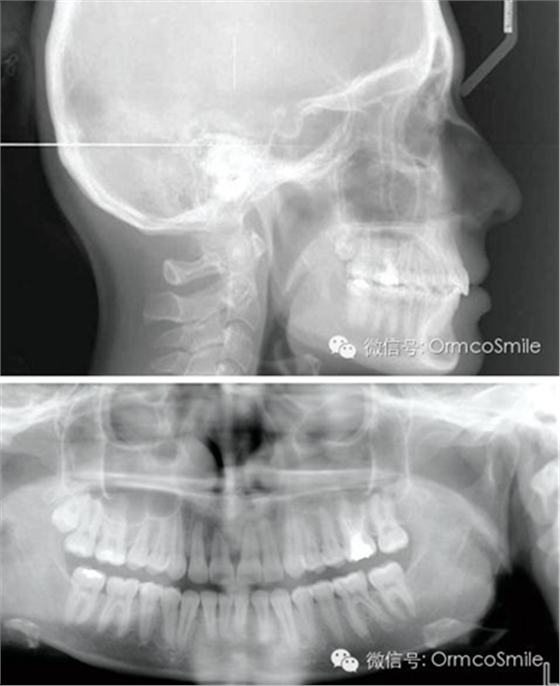

治療目標(biāo)為:遠(yuǎn)中移動(dòng)上頜右側(cè)磨牙,達(dá)到安氏Ⅰ類尖牙、磨牙關(guān)系。治療前,拔除上頜左側(cè)第三磨牙,將一直徑2mm,長(zhǎng)14mm的鈦骨釘植入上頜腭中縫,位于切牙孔后4-5mm,中線旁3-4mm。用1.3mm直徑的鉆助攻植入螺紋釘。一周之后,取印模并灌制模型,將螺紋釘?shù)念^部用蠟包圍,從螺紋釘上延伸出連接第一前磨牙的0.8mm的鋼絲??趦?nèi)試戴后,用光固化樹脂將從螺紋釘上延伸出的弓絲與上頜第一前磨牙粘接在一起,0.016*0.022英寸不銹鋼絲片段弓加鎳鈦推簧置于上頜第一磨牙和第一前磨牙間,每側(cè)250g力推動(dòng)上頜磨牙向遠(yuǎn)中,磨牙到位后拍攝頭側(cè)位片。

經(jīng)測(cè)量,上頜第一磨牙遠(yuǎn)中移動(dòng)3.5mm,達(dá)到磨牙Ⅰ類關(guān)系,同時(shí)壓低2mm,而第一前磨牙和上頜切牙沒有明顯的移動(dòng)。上頜第一前磨牙有3°的輕度前傾,這可能是由于上頜只植入了1顆螺紋釘?shù)脑颍髡叻治霾捎脙深w螺紋釘可以減少這種副作用。在上頜磨牙遠(yuǎn)中移動(dòng)過程中,下頜平面角減少了1°,且其持續(xù)到正畸治療結(jié)束。上頜牙弓寬度有輕度擴(kuò)大。